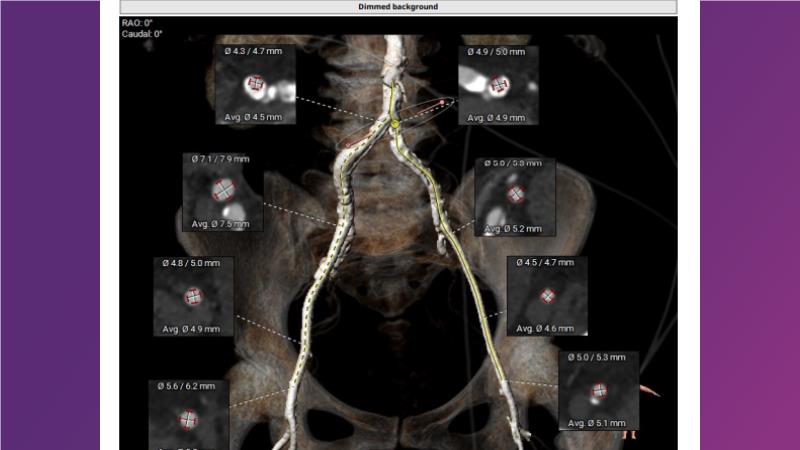

Gain expertise in selecting the appropriate TAVI device for achieving stable deployment in a 90-degree horizontal aorta. Discover techniques for ensuring smooth deliverability, particularly when navigating through tight and tortuous anatomies. Additionally, learn strategies to prepare for future coronary access, irrespective of the height of the left or right coronaries.

• To witness smooth deliverabilty even crossing tight and tortous anatomy